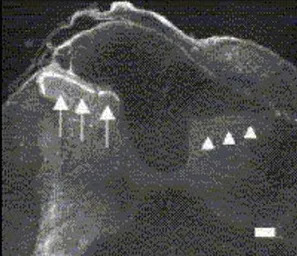

IHC analysis of rat spinal cord segment C6 using GTX10267 P2X3 antibody. Non-petidergic fibers expressing P2X3 receptor for ATP are present in lamina II of the contralateral dorsal horn (arrows). The P2X3-positive fibers are eliminated from the rat dorsal horn ipsilateral to the rhizotomy (arrow heads).

Dilution : 1:25,000